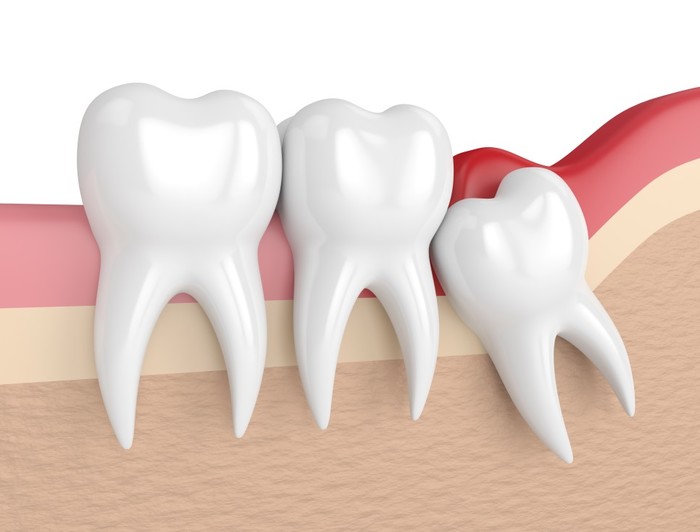

사랑니는 우리 입속에 가장 뒤에 난 어금니를 말하며, 전문용어로 설명해 드리면 제3대구치라고 하며 얼굴을 중심으로 좌우로 8번째 자리하고 있는 치아를 말합니다. 사랑니는 사춘기 이후에 자란다고 합니다. 사춘기에는 여러 가지 감정을 느끼게 되고 그 감정 중 하나가 사랑이라는 감정이지요. 그래서 이 치아를 사랑니라고 부른다고 합니다.

치과 치료를 하면 알 수 있는 것이 치아는 함부로 뽑지 않습니다. 정말 최대한 살려보고 그래도 안 되면 뽑아서 임플란트 등으로 빈자리를 채웁니다. 사랑니는 다른 치아들과 달리 발치를 해야 할 때도 있습니다. 잘 자란 사랑니는 특별한 문제를 일으키지 않아 뽑지 않아도 됩니다. 하지만 대부분의 사랑니는 말썽을 부립니다. 출혈, 염증, 통증 및 악취, 충치 들 여러 가지 문제를 일으킬 확률이 높기 때문에 뽑아야 합니다.